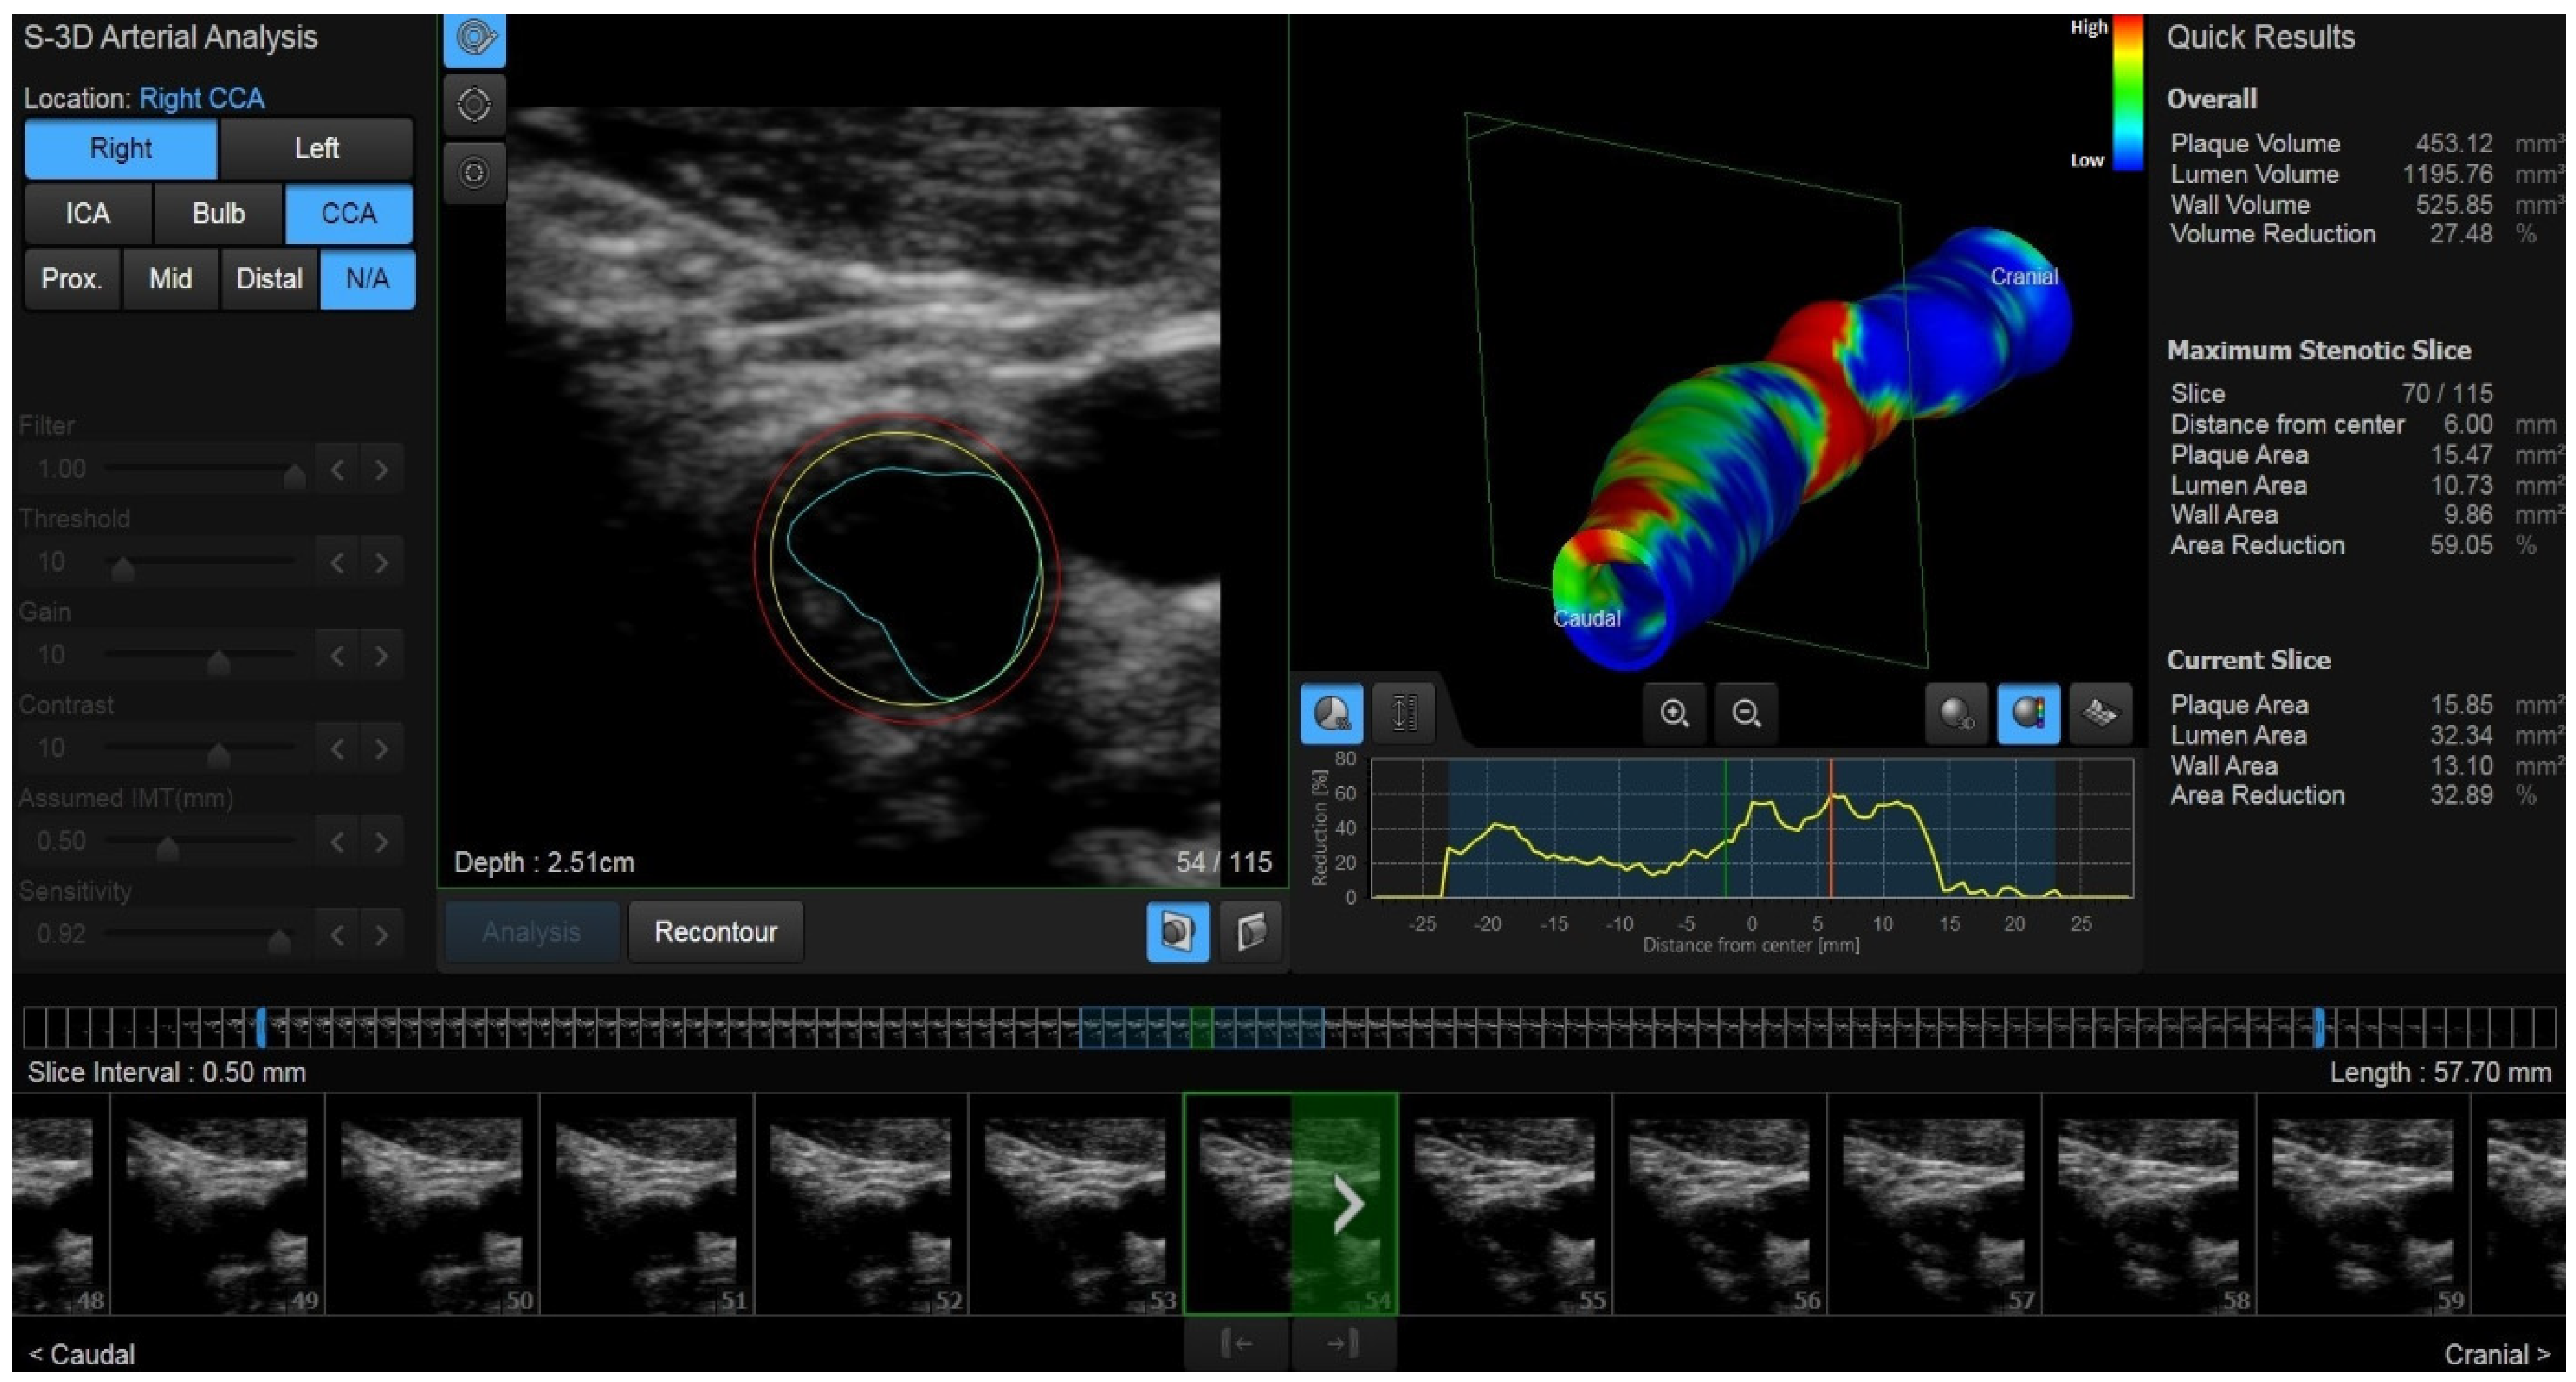

2.3. New Ultrasound Developments: 3D US and Vector Flow